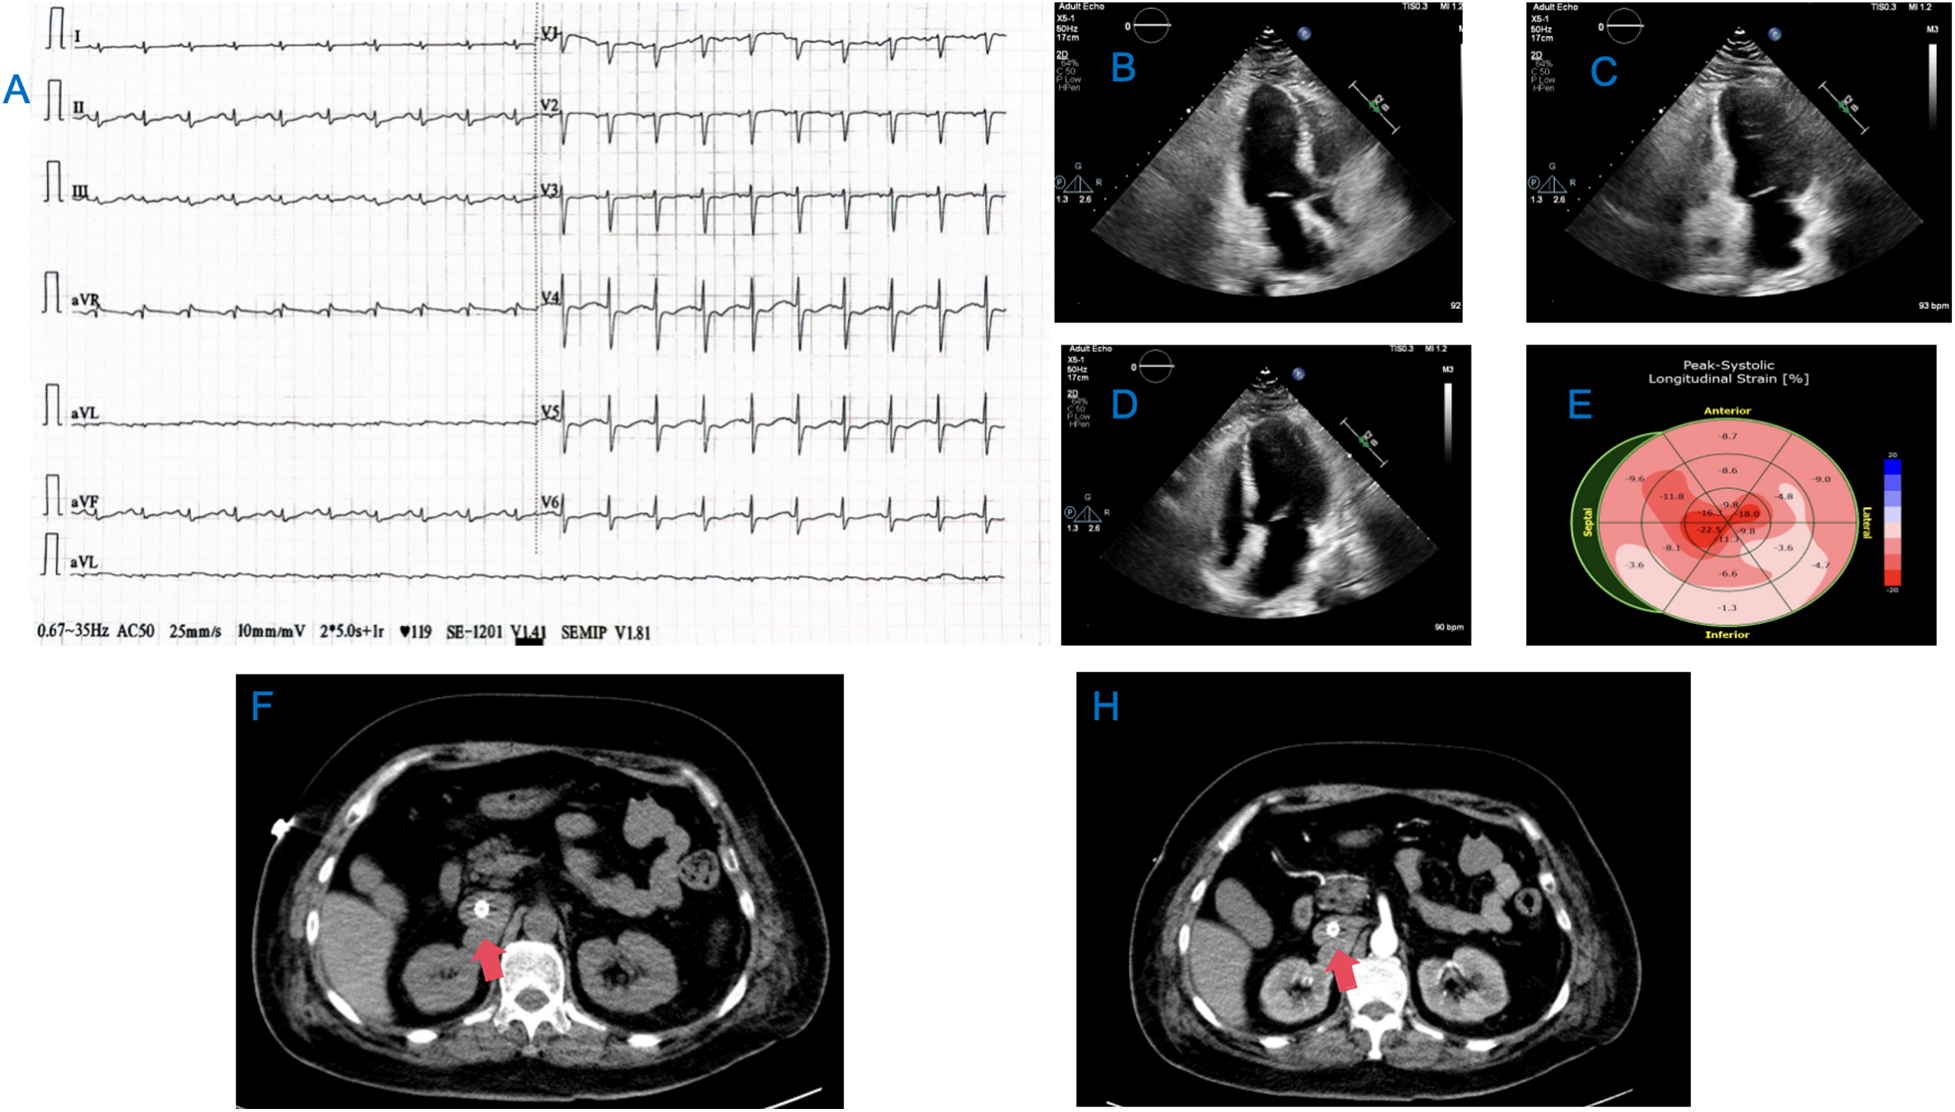

Figure 1

Results of the patient's ECG, cardiac ultrasound, and abdominal CT. (A) Sinus rhythm with ST segment depression and T wave inversion in leads V3-V6; (B–D) Ultrasound images of the patient's heart in the 2-chamber, 3-chamber, and 4-chamber views. (E) Graph of the Peak-Systolic Longitudinal Strain of the heart; (F,H) CT images of the patient's abdomen, with the red arrows indicating the PGL.

In the ICU, follow-up blood tests showed: CBC: rapid hs-CRP 0.66 mg/L, WBC 9.51 × 109/L, RBC 4.97 × 1012/L, arterial blood gas: pH 7.047, CO2 partial pressure 33.8 mmHg, oxygen partial pressure 53.1 mmHg, base excess −22.3 mmol/L, blood glucose (whole blood) 41.00 mmol/L, whole blood lactate 13.5 mmol/L; myocardial enzyme profile: creatine kinase 217 U/L, CK-MB 6.96 ng/ml, myoglobin 1,746.0 ng/ml, troponin 1.780 ng/ml, brain natriuretic peptide 273.0 pg/ml. Cardiac ultrasound indicated: left ventricular systolic dysfunction, significantly reduced basal activity, left atrial enlargement, EDV 98.41 ml, ESV 75.77 ml, LVEF 23% (Figures 1B–E). After a cardiology consultation, the diagnosis was considered acute left heart failure.

On the second day of admission, the patient's cardiac function progressively declined, leading to refractory cardiogenic shock, requiring high doses of inotropic drugs for maintenance, and frequent ventricular fibrillation. With family consent, V-A ECMO treatment was initiated. After successful ECMO initiation, the norepinephrine dose was gradually reduced and discontinued. Due to myocardial stunning post-ECMO, a small dose of epinephrine at 0.13 µg/kg/min was maintained. Catecholamine test results from the previous day (without any vasopressor drugs) (Table 1) showed: normetanephrine 1.87 nmol/L, metanephrine >10.14 nmol/L. Combined with the ECG, cardiac ultrasound, and coronary angiography results, we diagnosed the patient with rTTS due to abnormal catecholamine release. On the third day of admission, the patient's cardiac function showed some recovery, with no further increase in myocardial enzymes, and vasopressor drugs were discontinued. We then administered phentolamine at 0.2 mg/min to dilate blood vessels and reduce cardiac load. On the fourth day of admission, the patient was taken for a CT scan, which unexpectedly revealed a mass in the right retroperitoneal area (Figures 1F,H). After multidisciplinary discussions (MDT), we considered that the patient's recurrent dizziness and chest tightness over the past two years were due to abnormal catecholamine release, likely caused by the retroperitoneal mass. With family consent, right retroperitoneal mass resection was performed under ECMO support. Preoperatively, the patient was given adequate fluid resuscitation and gradually increased doses of alpha-adrenergic blockers. Considering the ECMO maintenance and the need for routine heparin anticoagulation, the high risk of intraoperative bleeding led to the decision to pause heparin 12 h before surgery and reassess coagulation function, showing an APTT of 24.6 s. On the seventh day of admission, right retroperitoneal mass resection was performed under ECMO support. Despite severe intraoperative bleeding, symptomatic treatment ensured a successful surgery. Pathology results indicated PGL (Figure 2). Postoperatively, the patient's vital signs were stable without PPGL crisis, and cardiac function recovered well, leading to ECMO removal on the eighth day of admission. After a period of ventilator training and symptomatic supportive treatment, the patient improved, and the tracheal tube was removed on the sixteenth day of admission. Finally, on the twentieth day of admission, the patient was transferred out of the ICU and successfully discharged after a series of rehabilitation treatments in the general ward. Figure 3 is a timeline of the clinical condition progress and major management of the patient. Table 1 presents the patient's levels of methoxamine, metaraminol, myoglobin, troponin, and BNP before admission, during hospitalization, and after the resection of the right retroperitoneal mass.